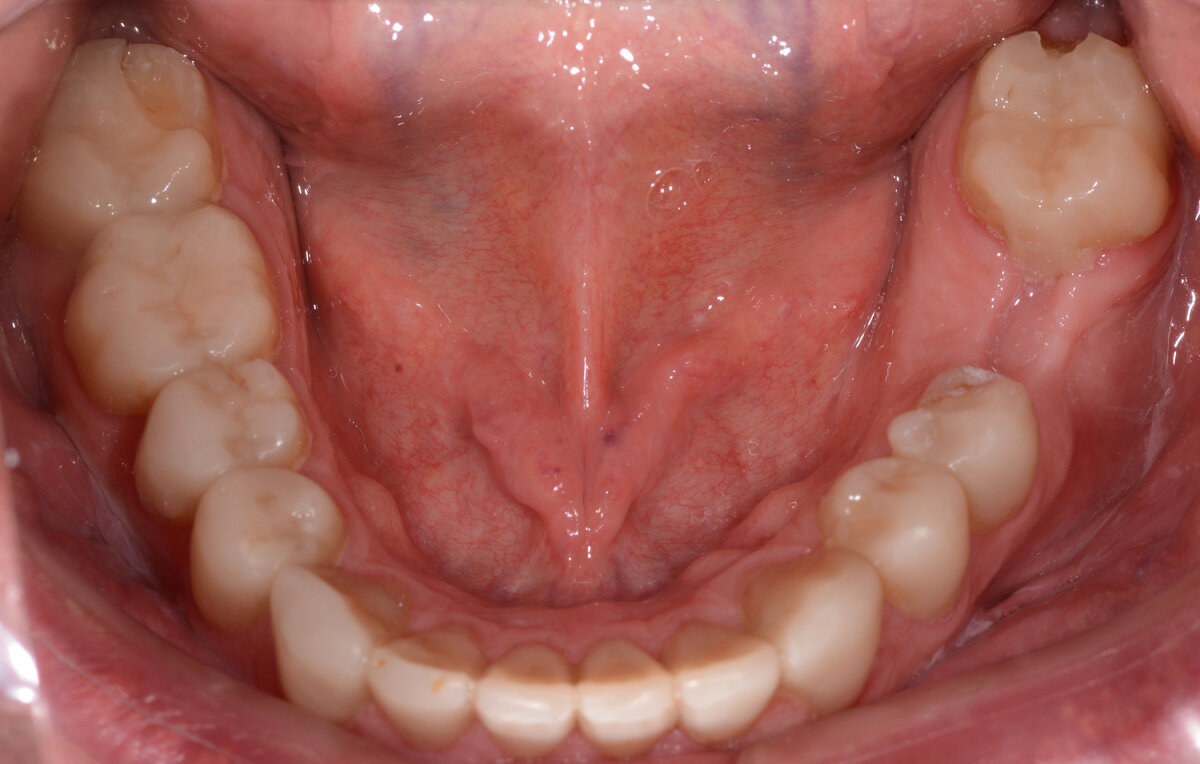

В клинику обратился пациент с жалобами на дискомфорт при пережевывании пищи. Эта проблема сопровождалась также потерей эстетического вида верхних зубов: они стерлись и потемнели.

Пациента больше волновал внешний вид зубов, но нашей целью было исправить все текущие проблемы в процессе лечения, избавить его от неприятных ощущений и подарить красивую улыбку.

Мы провели диагностику, компьютерную томографию, сделали необходимые фото ,чтобы определить объем работ. В первую очередь необходимо было удалить два проблемных зуба с воспалениями, которые были сильно разрушены, и установить на их место импланты.

Две старые коронки также подлежали снятию, так как были сделаны по старому прикусу и портили эстетику улыбки.

В местах сильной стираемости требовалось протезирование коронками с повышением прикуса. Снижение высоты прикуса (уменьшение расстояния между челюстями) неизбежно в процессе стирания зубов.

Каждая челюсть стерлась примерно до 4 мм (более 1/3 длины зуба) и для того, чтобы лечение прошло успешно, мы разделили его на несколько этапов.